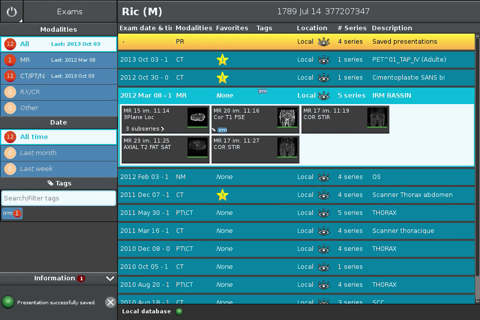

The Anywhere Streaming is now available as a free download on Apple Store for both iPhone and iPad owners.The application is supporting English language. It weighs in at a hefty 450560, so make sure you have plenty of free space on your iOS device. The new Anywhere Streaming app version 2.6.0 has been updated on 2016-04-24.

Anywhere Streaming is a DICOM visualization client that connects to Anywhere Server. It provide standard medical image navigation tools surch as : slicing, windowing, MPR, 3D VR, MIP, oblique ... All standard medical image modalities are ...